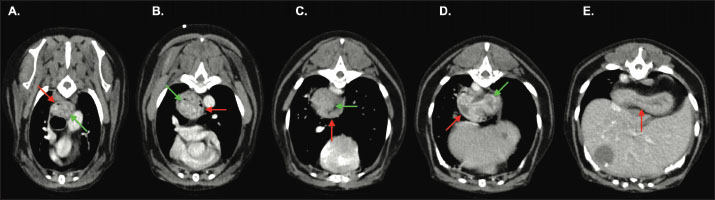

Pre-contrast acquisitions demonstrated a normally positioned stomach; however, the gastric fundus was cranially herniated through the oesophageal hiatus into the caudal esophageal lumen on the venous-phase post-contrast scan (Figs. 1 and 2). The distal oesophageal wall encircled part of the gastric fundus, creating a target-like appearance on transverse-plane images (Fig. 3). The orad oesophagus contained a small-to-moderate amount of heterogeneous fluid-to-soft-tissue-attenuating material. Delayed post-contrast images showed the stomach had returned to its normal anatomical position.

Fig. 1. Transverse (A), sagittal (B) and dorsal (C) images from the venous-phase acquisition. Part of the gastric fundus (green arrow) has herniated cranially through the oesophageal hiatus into the caudal thoracic oesophagus (red arrow). The gastroesophageal junction (blue arrow) remains in a normal position. The more proximal thoracic oesophagus is mildly distended by a small volume of heterogeneous, intraluminal, fluid-and-soft-tissue-attenuating material. Findings are consistent with gastroesophageal intussusception.